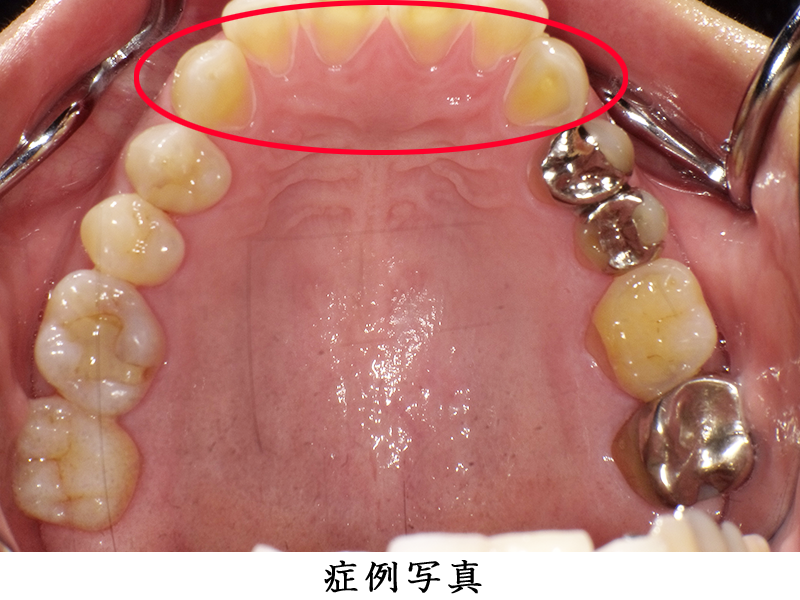

昨日上の歯の虫歯を抜歯したんですがこれはドライソケットでしょうか Yahoo 知恵袋